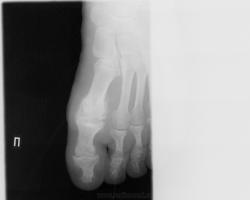

Похоже подагрический артрит, есть характерные тофусы

И я похожую на эту картинку подтвержденную подагру видела.